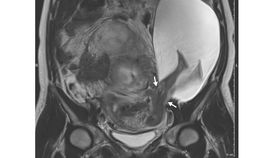

The rest of this article is behind a paywall. Please sign in or subscribe to access the full content.The case was about a 33-year old woman who was 22 weeks pregnant. Although she appeared to have no symptoms at first glance, routine ultrasound detected something unexpected. Subsequent magnetic resonance imaging showed that her uterine wall had a 2.5-centimeter-long (1 inch) rupture and the amniotic sac had herniated, letting the fetus's abdomen and legs to poke through.

The woman was treated by doctors at the Angers University Hospital in France, who said they had never seen anything quite like it before. She had had five previous caesarean sections. The scar tissue from these procedures was not found in the same location as this new rupture, however, the multiple C-sections are believed to have weakened the uterine wall.